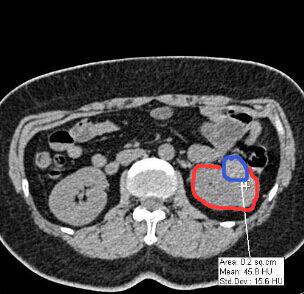

相信很多人和筆者一樣,還是感到疑惑,傳統(tǒng)拍片和3D打印出來的器官模型具體有哪些不同,后者又如何表示病變或者需要進(jìn)行手術(shù)的位置呢?對于這一點(diǎn),專業(yè)進(jìn)行3D設(shè)計(jì)和打印的東莞創(chuàng)客聯(lián)盟公司給讀者解答了這個疑惑。其負(fù)責(zé)人陳小姐表示,通過不同顏色來表達(dá)病變或需要進(jìn)行手術(shù)的位置,所打印出器官模型足以讓病變位置一目了然。為便于說明,其負(fù)責(zé)人展示他們做的一個案例:

某醫(yī)院的外科醫(yī)生需要做一個3D腎臟模型,但CT片拍出的二維圖像中,其腫瘤位置只是通過灰色的色階來表示(臨床應(yīng)用中稱之為CT值),如上圖中紅色圈出來的是腎臟截面,藍(lán)色則為腫瘤位置。從圖中可以看出,在CT片子中藍(lán)色部分僅僅比紅色部分要白一點(diǎn)。